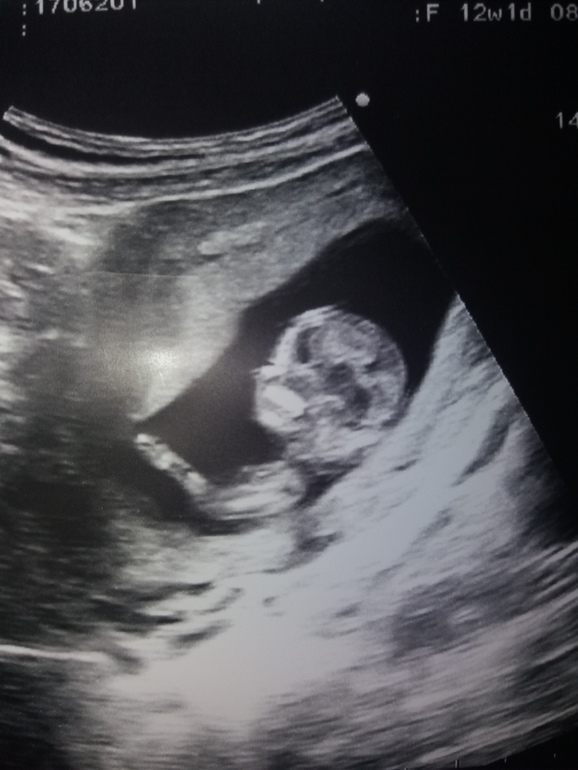

Пол малыша

Девчонки подскажите видно вам ли половой бугорок? у других вроде замечаю , а вот у себе нет ,фото по узи срок 10.2 , по М больше было , сегодня 12.2 после 1 скрининга сказали больше на мальчика .Есть фото за 12 недель но там я вообще не вижу, тут хоть что то вроде видно))) Если видно вам как думаете девочка или мальчик ? Знаю что предположения насчет пола не очень на маленьком сроке, но все же очень хочу уже своей ляльке делать прическе и нарядами баловать😏

первое фото 10.2

второе 12.2 (нед)(нед)